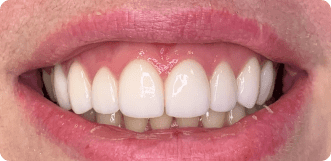

Caso 1

Reabilitação Oral

Neste caso, iniciamos a avaliação com fotos intra e extra orais, escaneamento intraoral e entendemos os desejos e receios do paciente.

Com o planejamento digital feito, mostramos todos os procedimentos necessários para o sucesso do tratamento escolhido pelo paciente.

Sendo assim, foram feitos 12 procedimentos diferentes nessa reabilitação oral.

outros ângulos do antes e depois

Lentes de contato

São laminados cerâmicos ultrafinos (entre 0,3 e 0,8 mm) de porcelana ou resina que são aplicadas sobre a superfície dos dentes para corrigir imperfeições estéticas, como cor, forma, tamanho ou pequenos espaçamentos.

Elas são personalizadas para cada paciente, proporcionando um sorriso natural e harmônico.

Com planejamento digital, sabemos onde é necessário desgastar o mínimo possível do dente a fim de ter o espaço exato para a porcelana se integrar perfeitamente ao seu sorriso e preservando a saúde gengival.